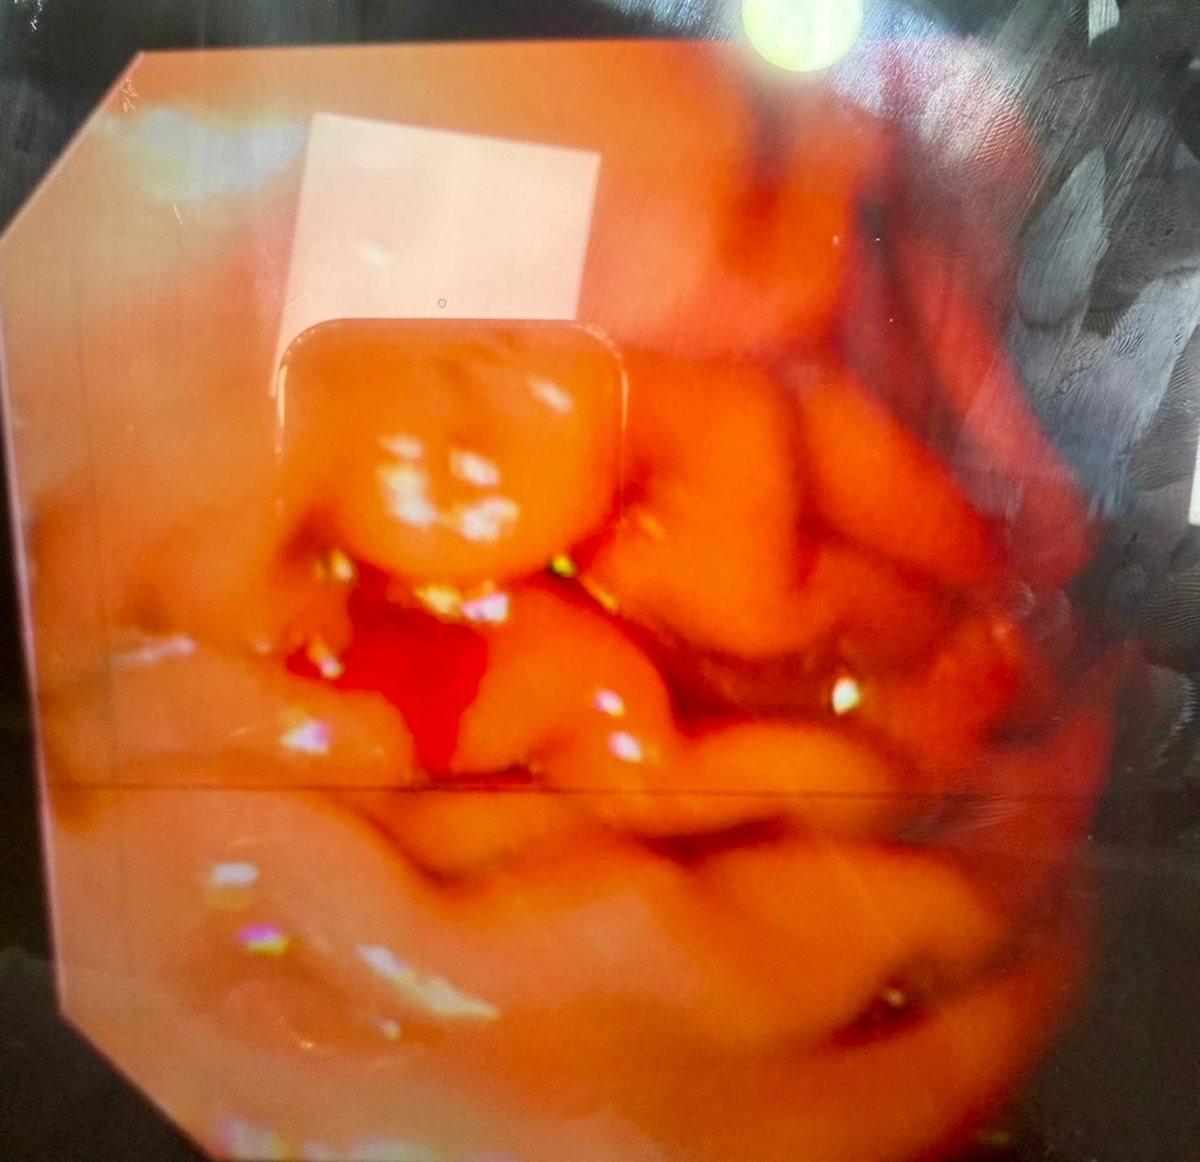

وأوضح د أسامة أحمد بلبل وكيل وزارة الصحة بالغربية أن الوحدة الجديدة تقدم خدمات مناظير الجهاز الهضمي العلوي للمرئ والمعدة، بالإضافة إلى مناظير الجهاز الهضمي السفلي، بما يساهم في تحسين دقة التشخيص وسرعة التدخل العلاجي للحالات. ويأتي افتتاح وحدة مناظير الجهاز الهضمي والكبد امتدادًا لخطة التطوير الشامل للمستشفى، ودعمًا لرفع كفاءة الخدمات المقدمة لمرضى محافظة الغربية والمحافظات المجاورة.